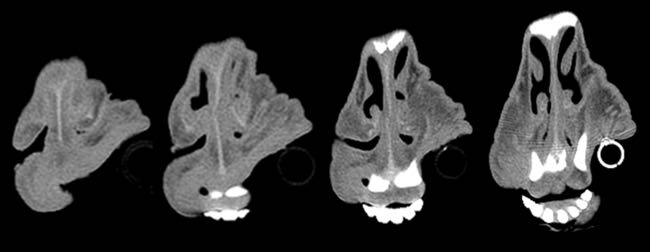

Given the clinical findings and prior experience with upper airway disease, ancillary tests were performed. Thermography did not identify consistent focal increases in temperature across the six animals, making common differentials such as chronic proliferative rhinitis (CPR) or enzootic nasal adenocarcinoma (ENA) less likely. Oestrosis had also been ruled out, as previous treatments targeting this condition failed to result in clinical improvement in the affected animals. Computed tomography (CT) of the head revealed increased soft tissue in the rostral nasal cavity, producing variable obstruction of the nasal meatuses in all sheep. On transverse CT images, soft-tissue thickening causing luminal narrowing was confined to the most rostral nasal cavity and decreased progressively on more caudal slices, where the nasal airway regained a wider lumen (Figure 3). This localisation of obstruction at the alar fold level explained the inspiratory dyspnoea and snoring.

Figure 3. (2 images) Serial images obtained from the computed tomography scanner with different filters. Four sequential cuts of two sheep, from rostral (left) to caudal (right), show increased cellularity and almost complete blockage of the airway in the rostral area, which diminished as the images progress caudally.